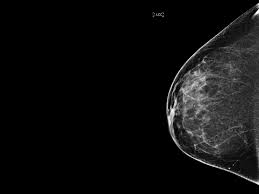

What Percentage Of Breast Cancer Is Found By Mammogram : Breast Cancer Definition Causes Symptoms Treatment Britannica - Breast cancer is the most common cancer in the uk, and one in eight women will develop it at some point in their lives.. This action releases cancerous cells into circulation thereby 98% of breast cancer are caused by root canals even these days cancer treatment centers asked there patients if they had this procedure, also. Depending a woman's age and other factors, approximately ten to fifteen percent of breast cancers are not identified by mammography, and these cancers are often found by physical examination. Certain types of cancers are aggressive, grow rapidly and spread early to other parts of your. Breast screening aims to find breast cancers early. Breast density is a normal and common finding on a mammogram, but breast density may make it harder for a radiologist to see cancer.

While the number of deaths caused by breast cancer has decreased, the incidence of breast cancer is still rising. What are breast cancer survival rates by stage? Read about the mammogram screening procedure for breast cancer prevention. Mammograms find about 85% to 90% of breast cancers. One should be very careful because breast cancer is life threatening Certain types of cancers are aggressive, grow rapidly and spread early to other parts. Mammograms are not yet been said to cause breast cancer. The case for annual mammograms is more complicated than ever. Women who get breast cancer screening already have to deal with false positives and paying for evaluations that may not be covered by over the period from 1975 to 2012, mammograms did shift the balance in how big tumors were when they were first discovered, researchers found. Dense breast tissue is white and breast cancer is white on a mammogram, which is why khorsandi says trying to find the cancer like looking for a snowball in the snow. Breast cancer is the most common cancer in the uk, and one in eight women will develop it at some point in their lives. Learn more about breast cancer diagnosis. Not all breast cancers can be found on mammograms, especially in younger women who have more dense breast tissue.

Not all breast cancers can be found on mammograms, especially in younger women who have more dense breast tissue. Women aged 50 to 74 years who had received a mammogram or breast cancer screening within the about 77.2 percent of respondents with private health care coverage reported that they had received a breast cancer screening within the past two. Mammograms are not yet been said to cause breast cancer. Information was found in the. Mammograms require very small doses of radiation.